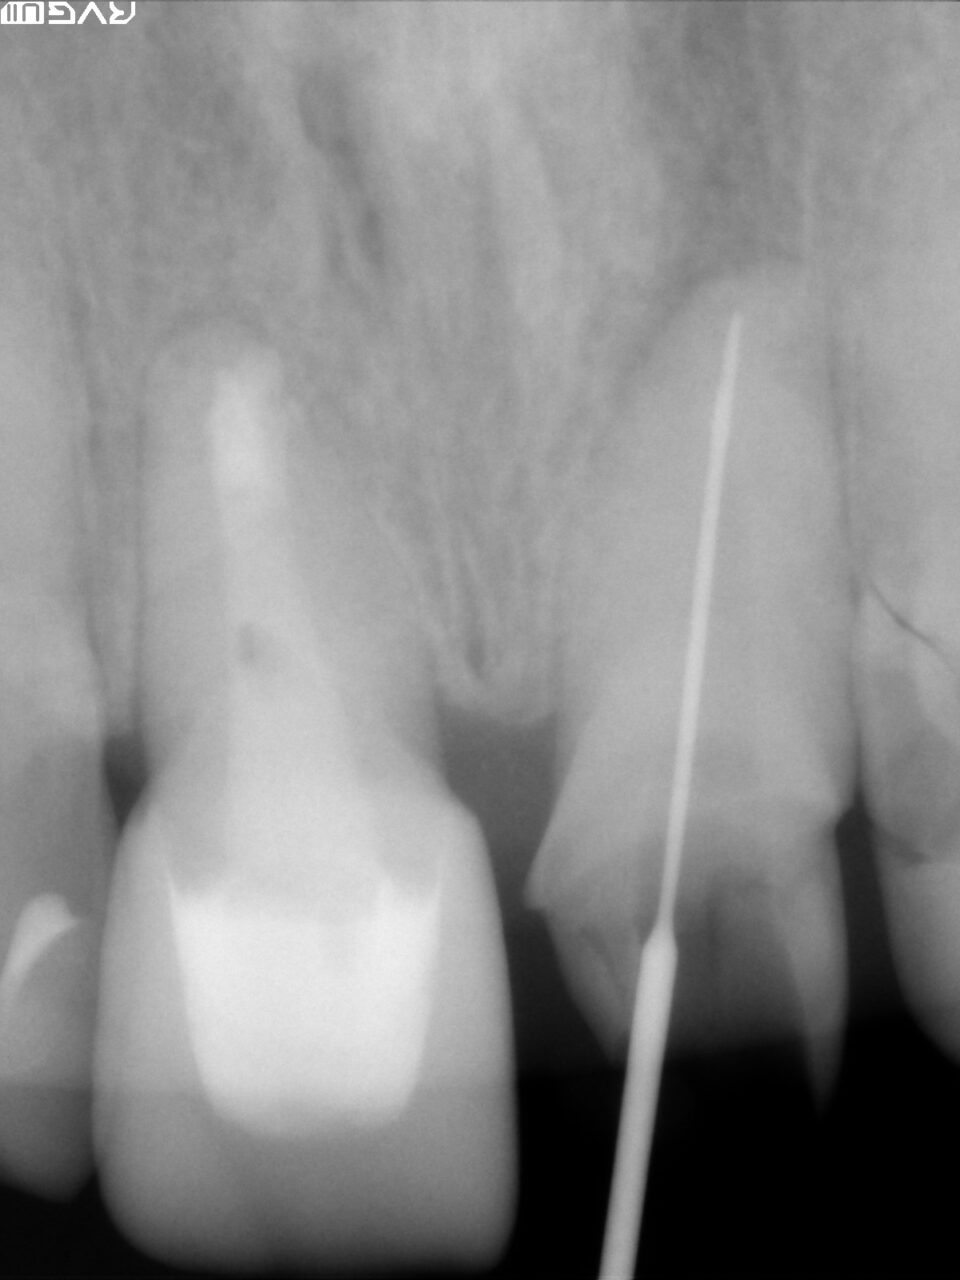

根尖までファイルが到達した事を確認するためにレントゲンを撮り、根尖孔の太さや根管の長さを確認しました。